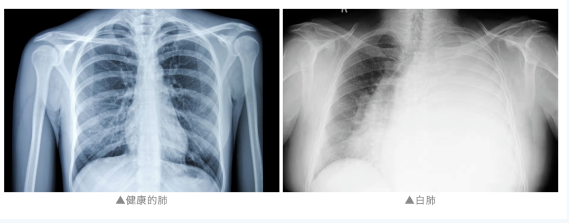

通常来说

“白肺”是指急性呼吸窘迫综合征

主要发生在重症感染时

双肺弥漫性病变进展迅速